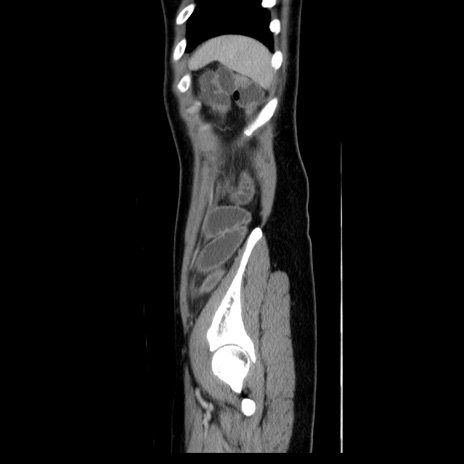

症例39(矢状断像)

【症例】40歳代女性

【主訴】上下腹部痛

【現病歴】2日目から下腹部痛あり。夜間は痛みで眠れなかった。昨日より上腹部痛と下痢が出現。臥位で痛みは軽快したため、休んでいた。本日になって臥位でも立位でも痛みが強くなってきたため救急要請。

【既往歴】子宮内膜症

【身体所見】部:平坦・軟、左上下腹部に圧痛あり、反跳痛あり。

【データ】WBC 21800、CRP 26.78

CT

MRI(4日後)